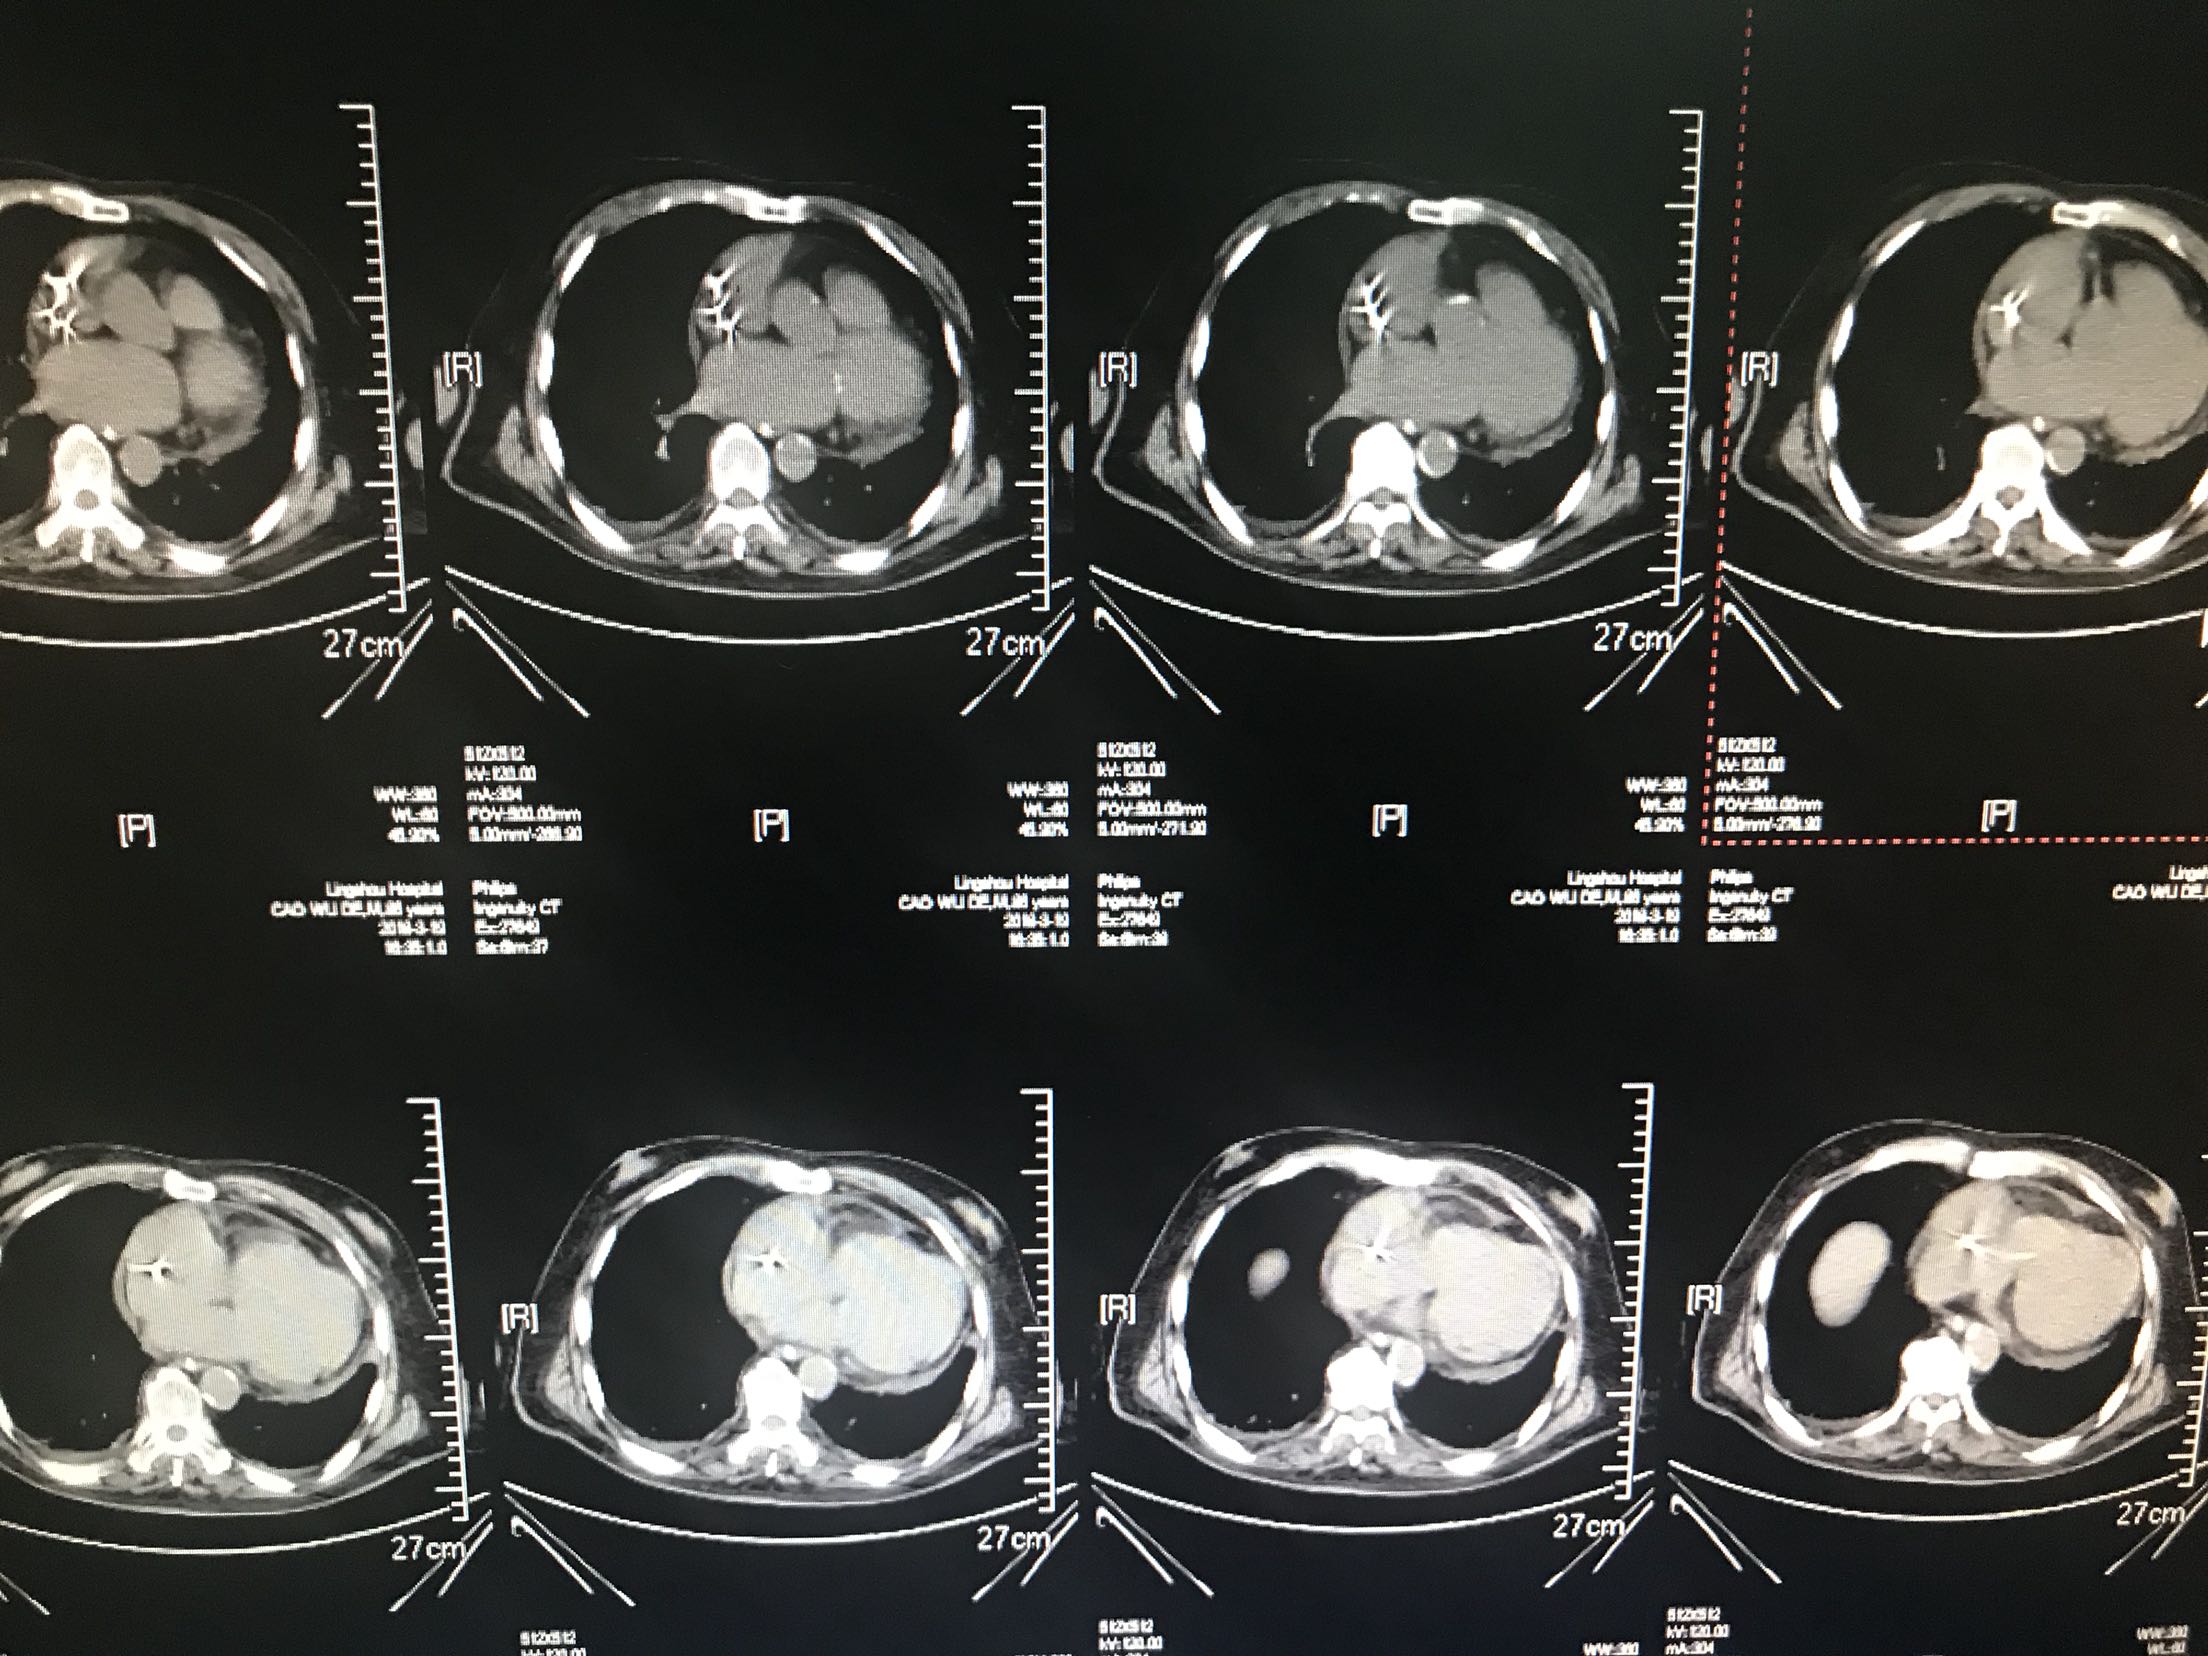

患者88岁不能行走1小时入院,房颤心衰起搏器安装痴呆病史,患者1小时前被家人发现倒在地上,不能言语,不能行走,急诊查血压210/120mmhg,查透头颅Ct够收住院

体温37.5℃脉搏95次/分,呼吸22次/分,血压135/87mmhg,意识模糊,,眼动充分,无明显眼震,颈无抵抗,双肺呼吸音清,未闻及干湿性啰音,心音低钝,心律不规整,未闻及杂音,双下肢可见不自主运动,霜巴氏征阳性,克氏征阴性,